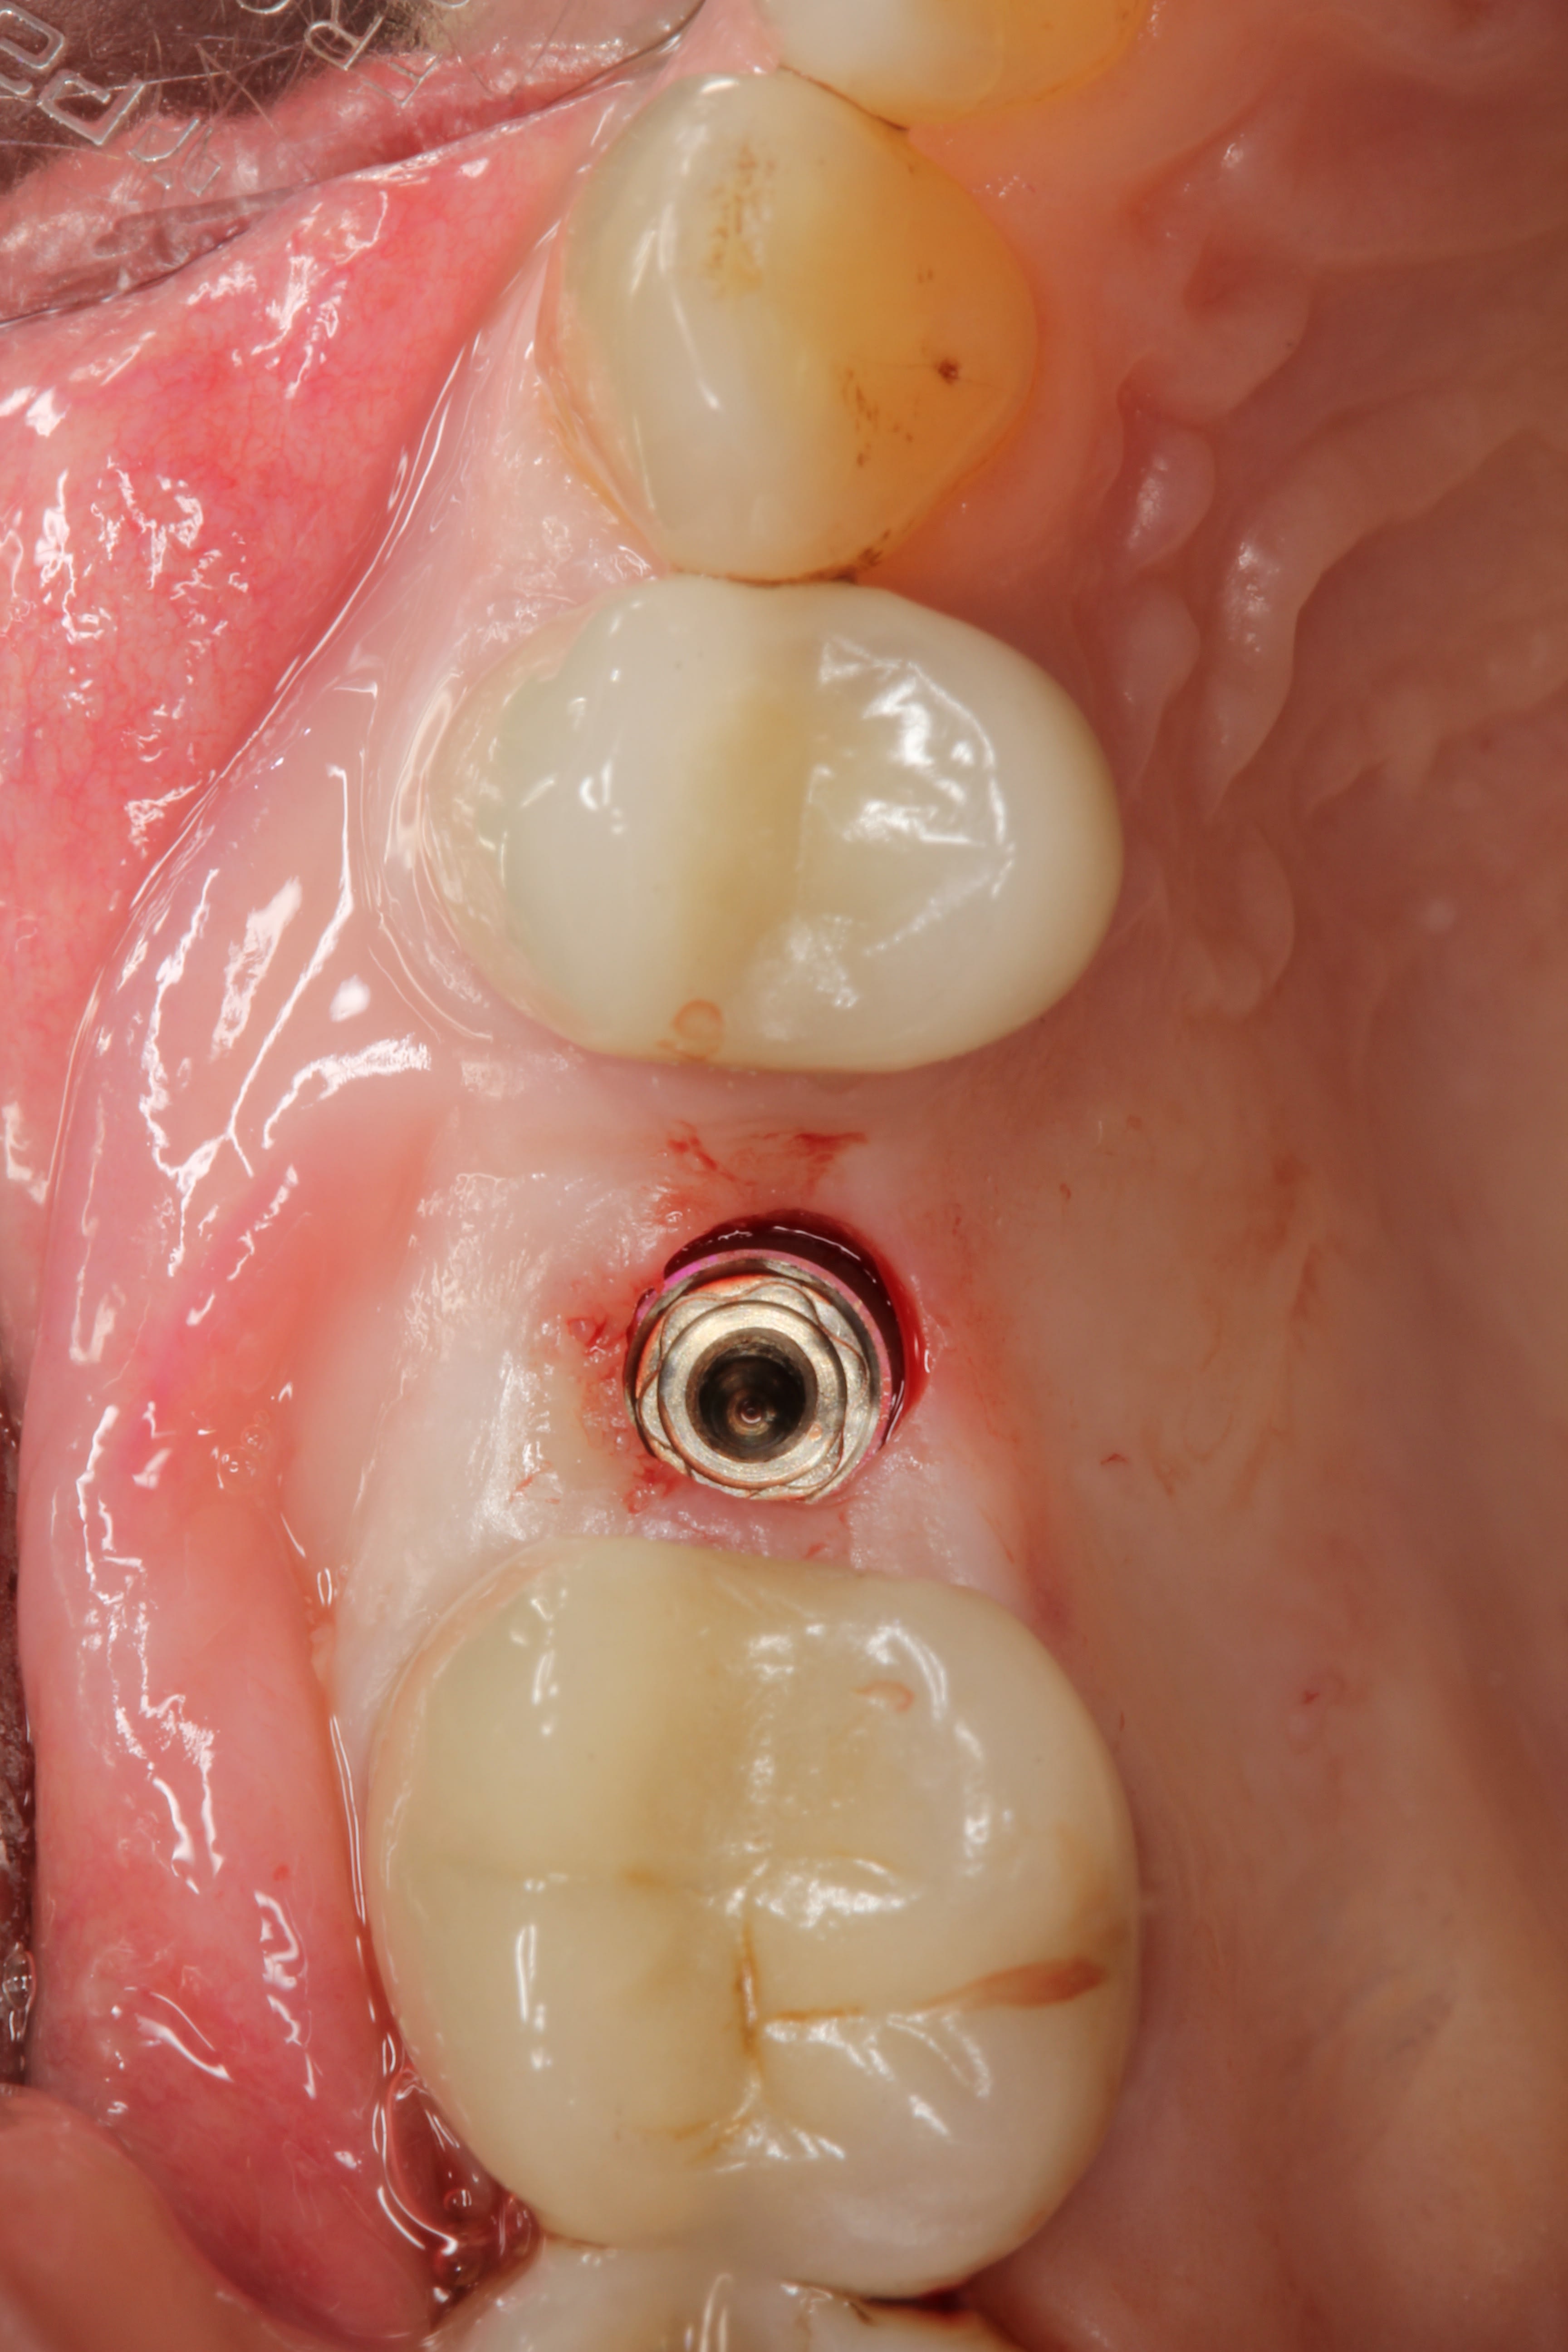

In February 2012 the patient enrolled in the multicenter study. Using a flapless access approach with the patient under nitrous-oxide sedation, one of the periodontist authors (ETS) removed keratinized tissue from the proposed implant site using a 4-mm biopsy punch. Osteotomy was prepared using a surgical guide for the placement of a 4.5-mm x 10-mm tapered implant (Genesis), which was anchored in the floor of the maxillary sinus (using osteotomes) for optimal primary stability, at an insertion torque of 45 Ncm (Figure 32).